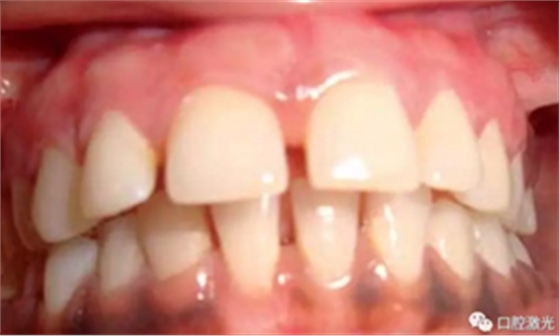

术前